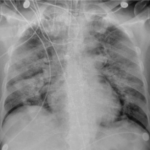

What does COVID look like on a chest xray?

(RSNA) Case example of diffuse non-specific airspace opacities in both lungs in an intubated patient with confirmed COVID diagnosis on day 6...